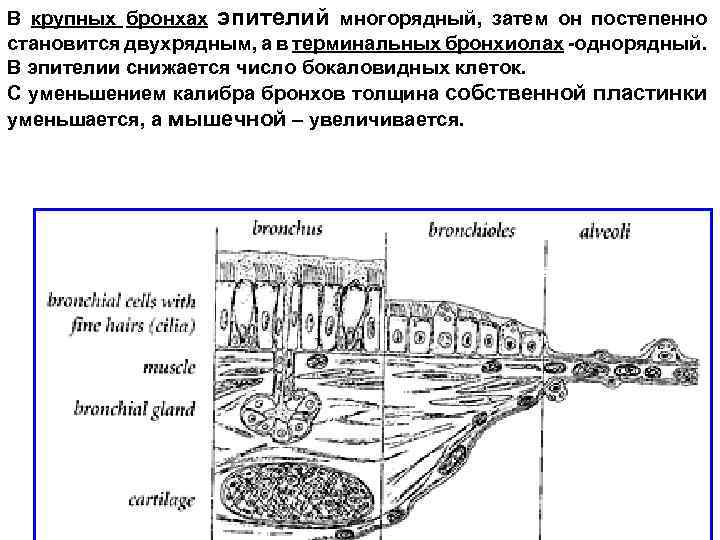

В крупных бронхах эпителий многорядный, затем он постепенно становится двухрядным, а в терминальных бронхиолах -однорядный. В эпителии снижается число бокаловидных клеток. С уменьшением калибра бронхов толщина собственной пластинки уменьшается, а мышечной – увеличивается.